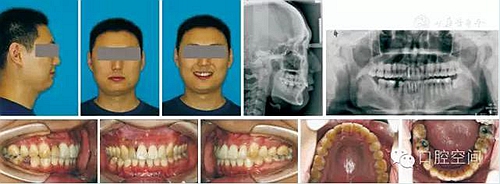

30歲男性患者,由于下前牙經(jīng)常咬傷上牙腭側(cè)牙齦,要求矯正調(diào)整咬合關(guān)系。上頜粘接直絲弓矯治器2個月后,下頜開始固定矯治,排齊牙列。4個月后下頜更換至0.018英寸鎳鈦絲,在下頜中切牙之間前庭溝處,局麻下切開黏膜,正中聯(lián)合部位植入一顆微螺釘(1.6 mm×9 mm,慈北醫(yī)療器械有限公司)。以直徑0.30 mm結(jié)扎絲連接微螺釘頭部,并穿出黏膜形成牽引鉤形狀。一周后開始加力,以微螺釘種植體支抗行閉合式牽引壓低下頜切牙。10個月后下切牙壓低良好,前牙覆頜正常,去除支抗螺釘。固定矯治20個月后,進入保持階段?;颊呙骖M像、X線片及頭影測量重疊圖見圖4,圖5,圖6,圖7,圖8,圖9,治療前后頭影測量結(jié)果見表2。

圖4病例1治療前面像及X線片

圖7病例1治療后面像及X線片